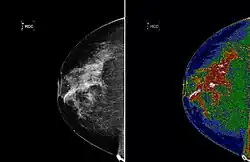

A region of interest (often abbreviated ROI) is a sample within a data set identified for a particular purpose.[1] The concept of a ROI is commonly used in many application areas. Existing as a vicinity, or within one. For example, in medical imaging, the boundaries of a tumor may be defined on an image or in a volume, for the purpose of measuring its size. The endocardial border may be defined on an image, perhaps during different phases of the cardiac cycle, for example, end-systole and end-diastole, for the purpose of assessing cardiac function. In geographical information systems (GIS), a ROI can be taken literally as a polygonal selection from a 2D map. In computer vision and optical character recognition, the ROI defines the borders of an object under consideration. In many applications, symbolic (textual) labels are added to a ROI, to describe its content in a compact manner. Within a ROI may lie individual points of interest (POIs).

Medical imaging

Medical imaging standards such as DICOM provide general and application-specific mechanisms to support various use-cases.